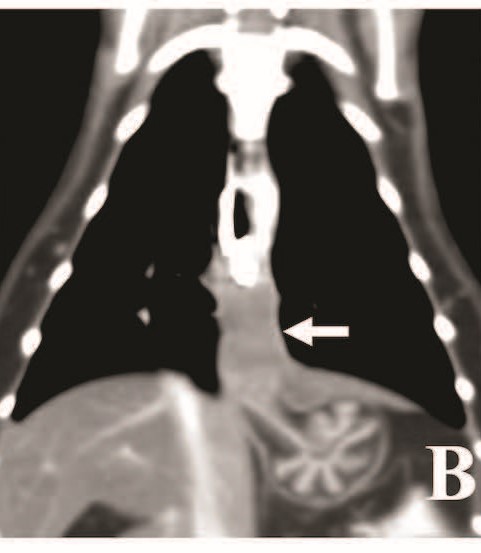

CT检查采用静脉注射1-2 mg/kg阿法沙龙诱导麻醉,七氟烷维持,发现膈肌头侧约2.5 cm肿块,考虑源于食管,可能是食物反流的原因。增强CT显示肿块轻度强化,三维重建图像可见肿块与胃黏膜相延续(图1B)。腹部CT中,肝脏CT值明显低于胆囊,提示长期饥饿诱发肝脂肪变性。

图1. (B) 胸腔三维重建冠状位CT,近端食管腔内含有硫酸钡,远端食管肿块似乎与胃黏膜相连(箭头)。